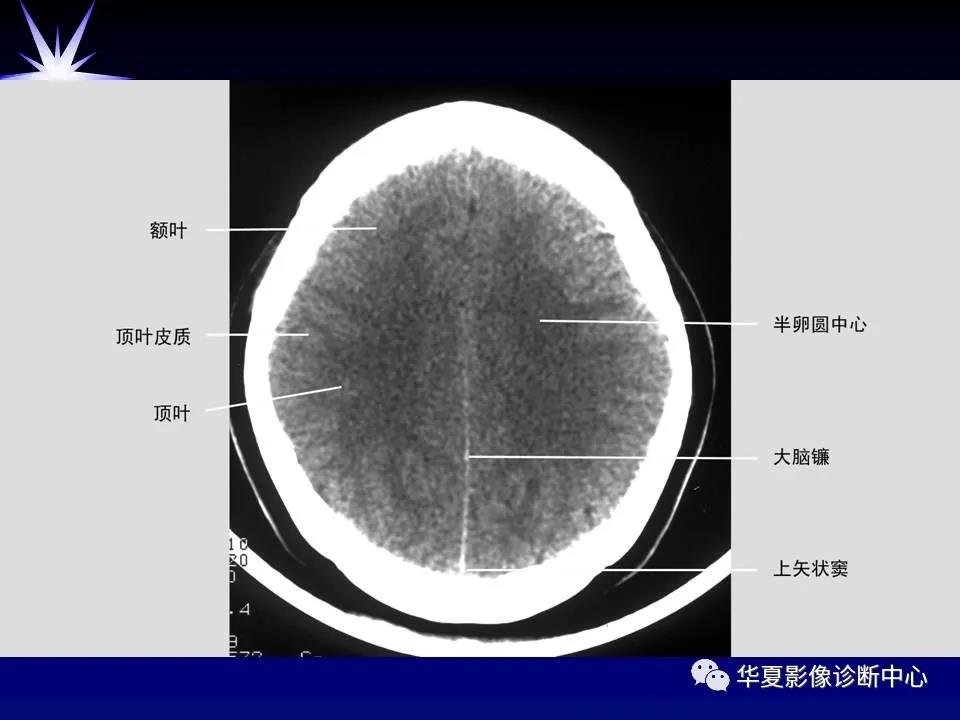

来源:华夏影像诊断中心